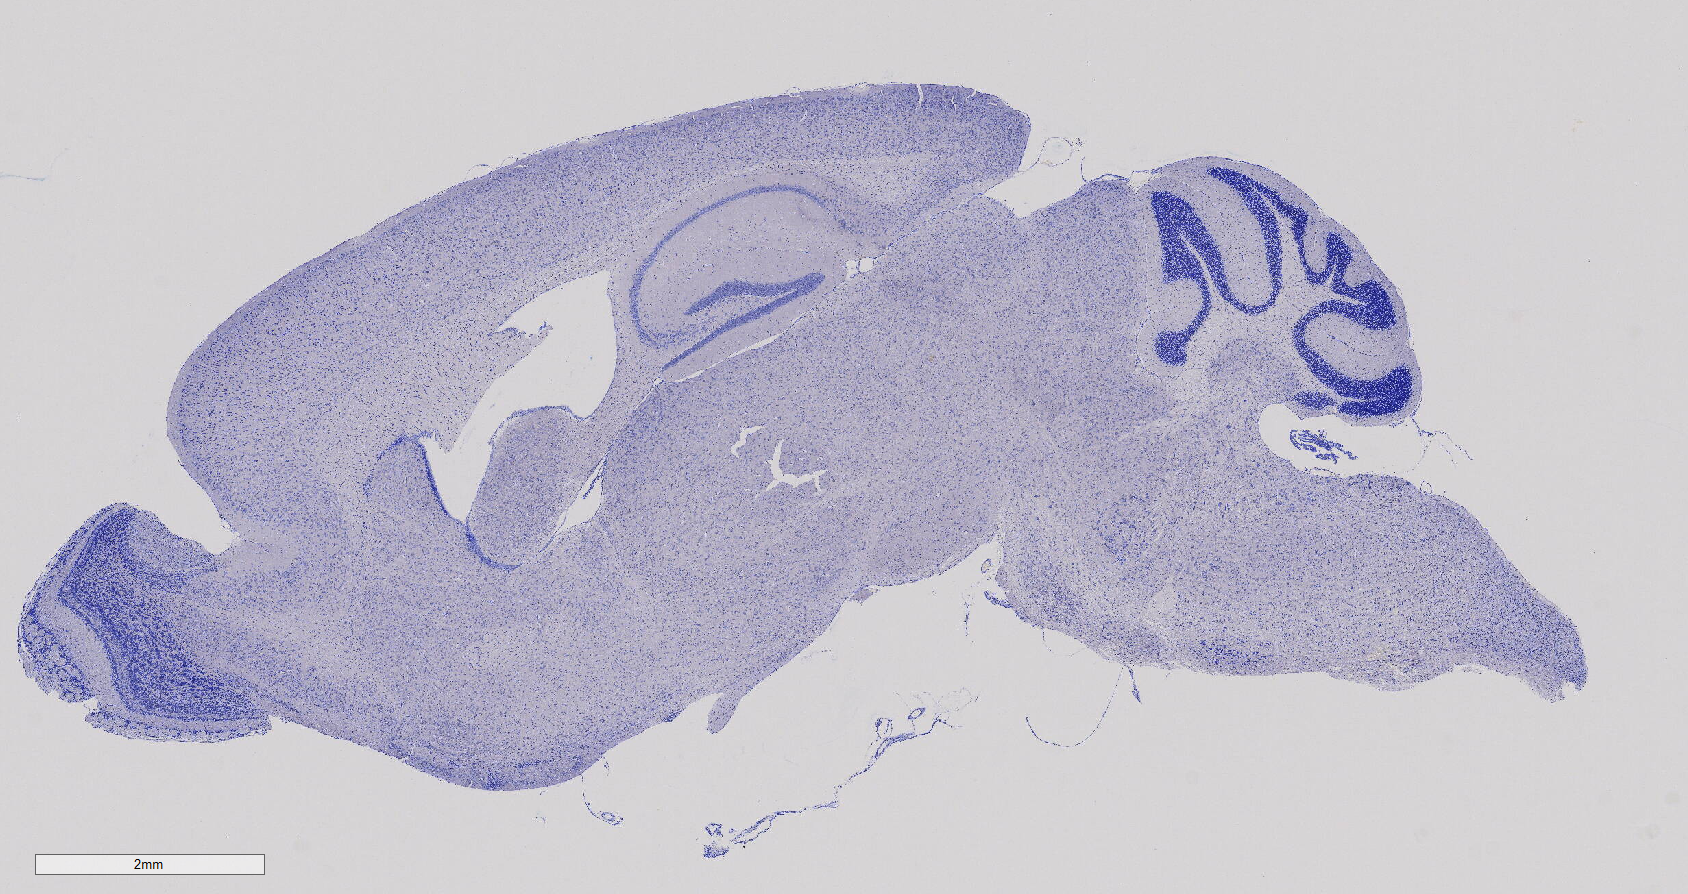

尼氏染色

尼氏染色法利用碱性染料对神经组织进行染色,以强调细胞质中的尼氏体。尼氏体是一种嗜碱性物质,分布广泛于各类神经元中,其形状、大小和数量在不同神经元中呈现差异。通过运用尼氏染色法,能够有效染显尼氏体,从而观察神经元内的细胞结构,并通过对尼氏体的观察来评估神经元是否受损。焦油紫、亚甲蓝、甲苯胺蓝和硫堇等是常用的碱性染料。这一技术为深入研究神经组织提供了强大的工具,使科学家得以更全面地了解神经元的结构和状态。

小鼠脑部整体尼氏染色 海马结构 尼氏小体